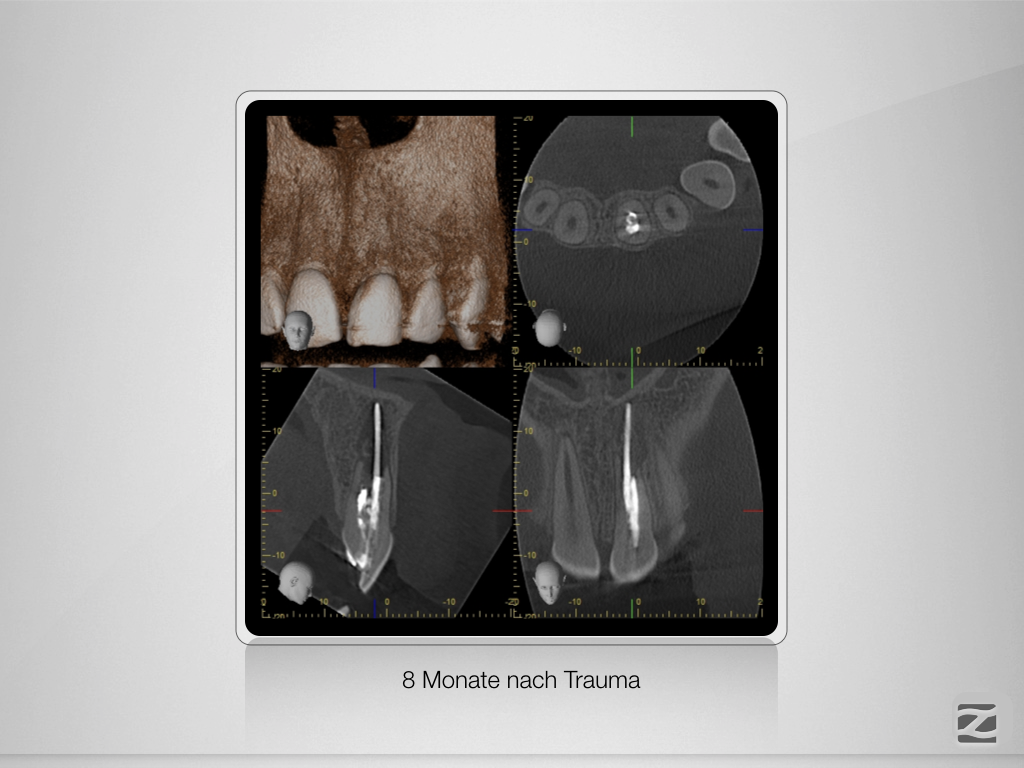

21D.005

Traumspätfolge